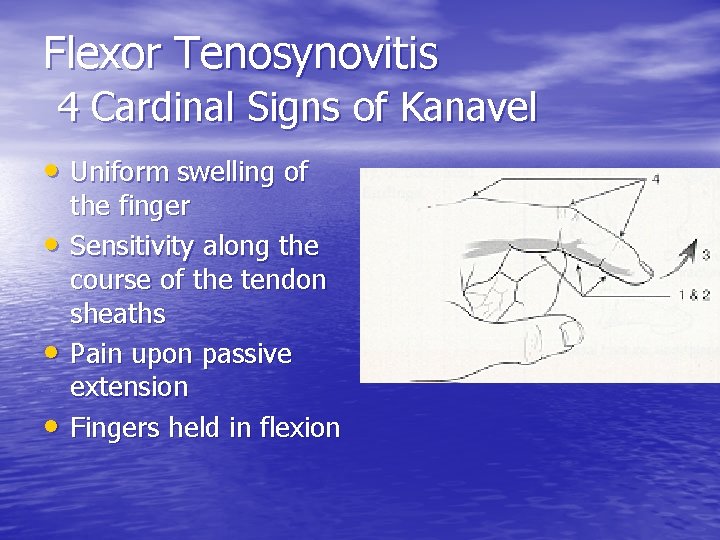

Flexor Tenosynovitis 4 Cardinal Signs of Kanavel • Uniform swelling of • • • the finger Sensitivity along the course of the tendon sheaths Pain upon passive extension Fingers held in flexion